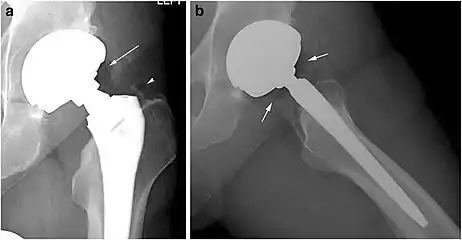

X-ray of a hip with hip replacement and pneumarthrosis, in this case aseptic.

A vacuum sign, or vacuum phenomenon, is a normal finding on shoulder X-rays.